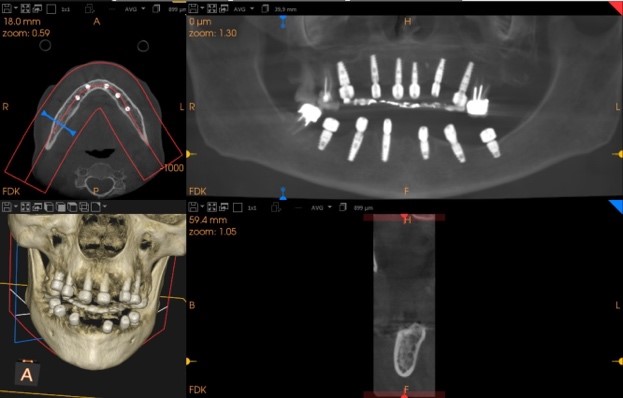

Una paziente di 65 anni si presentava presso la nostra clinica con ampie aree edentule (1° e 3° quadrante), un ponte con mobilità nel 2° quadrante e denti inferiori con scarso supporto parodontale ad eccezione del dente 46 (Fig. 1 a,b,c,d). Dopo un'accurata anamnesi ed esame della CBCT (CS9600®, Carestream Dental, Atlanta, USA) (Fig. 1d), si optava per estrarre le radici e i denti con una prognosi sfavorevole, lasciando 4 molari che credevamo potessero essere conservati (denti 16,17, 26 e 47) al fine di mantenere la dimensione verticale di occlusione (DVO) originale. Si progettava il posizionamento di 12 impianti: 6 impianti nella mascella e 6 nell'arcata inferiore.

Situazione pre operatoria 4

Fig. 1(d) Situazione pre-operatoria.